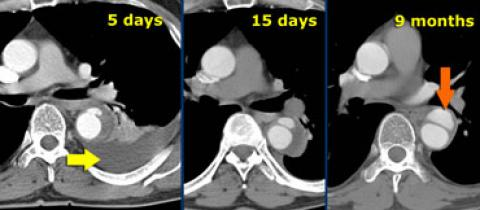

Pseudoanévrisme

- Se forment à distance